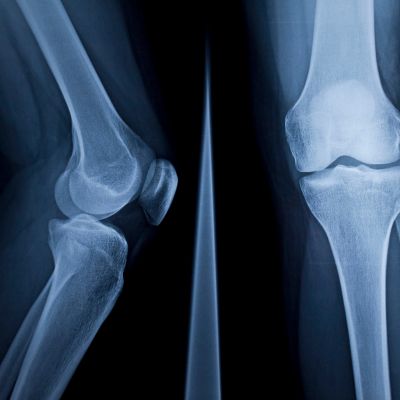

If you’re like one in five Americans, you’ll eventually develop arthritis of the knee. This means the cartilage that cushions the bones of your knee begins to degrade, causing those bones to painfully rub together. When that pain becomes too much or restricts activities you once enjoyed, it’s time to talk to your doctor about treatment, including knee replacement surgery.

Sometimes arthritis affects the entire knee joint, but often it degrades just one area (the inside or outside of the knee or even just the kneecap). During total knee replacement surgery, the surgeon removes the damaged cartilage and bone from the entire knee joint, then replaces the joint with a metal and plastic prosthesis (implant).